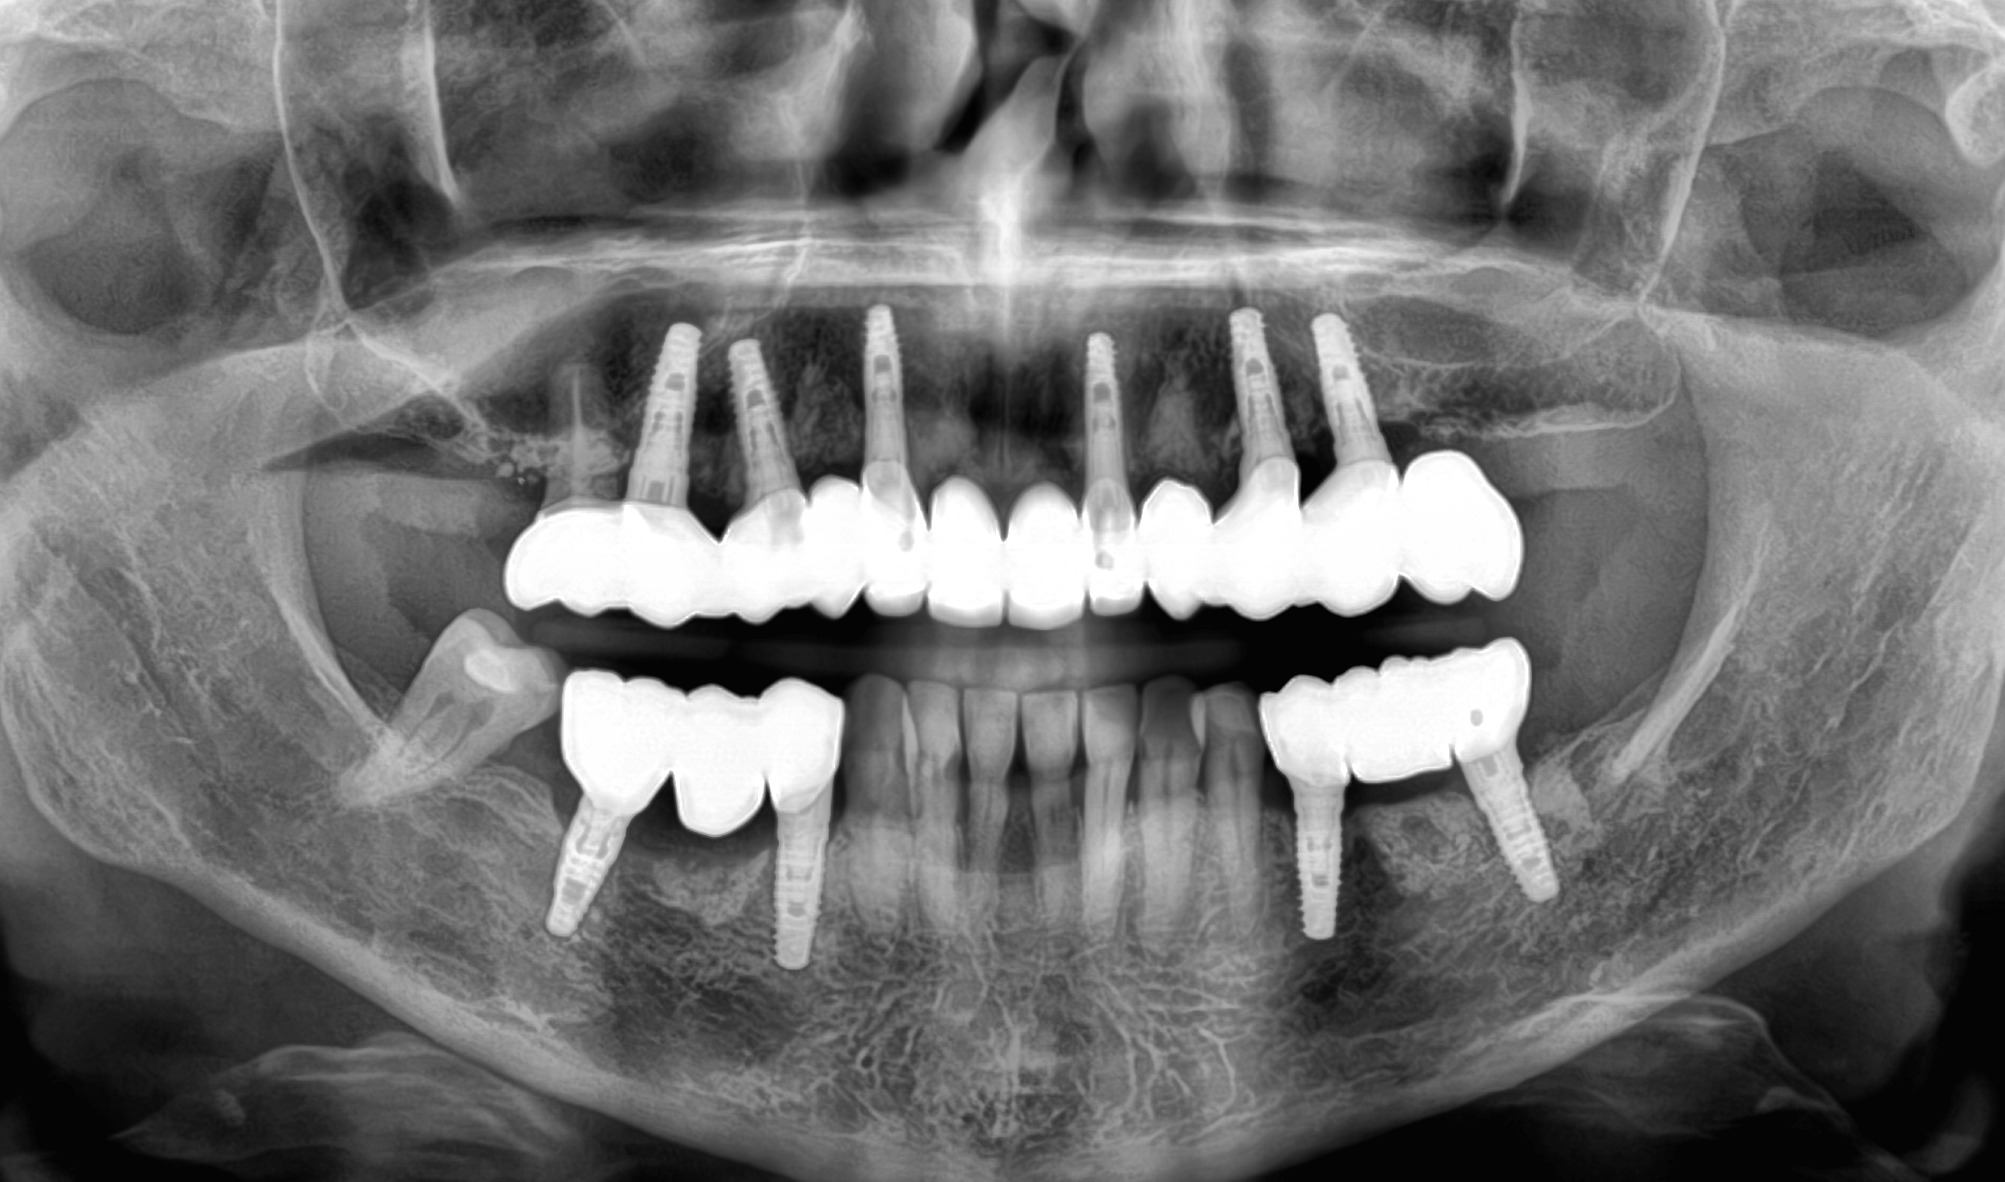

A causa di vari problemi di salute, la paziente si trova in una situazione di edentulia completa in entrambe le arcate. Le attuali protesi mobili sono per lei fonte di forte insicurezza a causa della loro mobilità. Nonostante la scarsità di osso mascellare e la presenza di viti di osteosintesi nella mandibola si procede con una riabilitazione fissa su entrambe le arcate combinando impianti tradizionali (mandibola) con impianti iuta-gengivali, nella mascella.

DOPO